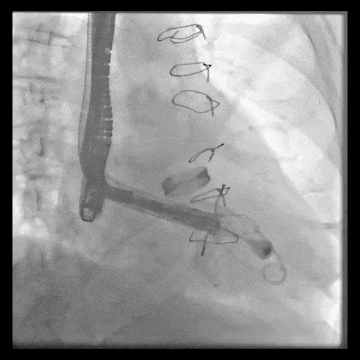

術(shù)中DSA顯示起搏器導(dǎo)線的干擾,右心室造影確定瓣環(huán)位置,操作空間小

術(shù)后DSA